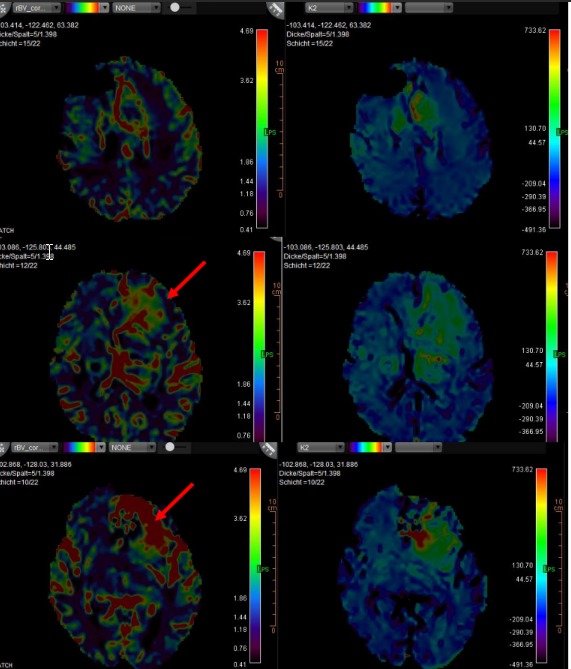

脑部MRI第二意见

- 高级神经影像脑部MRI复查 · 复杂神经系统病例

- 复杂脑部病变诊断明确化

多发性硬化与白质病变